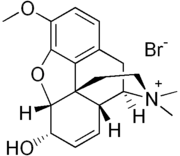

Several semi-synthetic opioids were developed in Germany in the 1910s. The first, oxymorphone, was synthesized from thebaine, an opioid alkaloid in opium poppies, in 1914.[228] Next, Martin Freund and Edmund Speyer developed oxycodone, also from thebaine, at the University of Frankfurt in 1916.[229] In 1920, hydrocodone was prepared by Carl Mannich and Helene Löwenheim, deriving it from codeine. In 1924, hydromorphone was synthesized by adding hydrogen to morphine. Etorphine was synthesized in 1960, from the oripavine in opium poppy straw. Buprenorphine was discovered in 1972.[228]